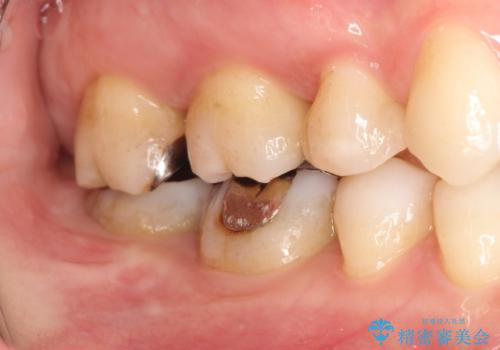

メタルフリー セラミックインレーによる治療

- 金属の詰め物を白くしたいと来院された患者様です。

セラミックインレーによって治療を行いました。

当院でのセラミックインレーはすべてe-maxと呼ばれる高強度セラミックにて製作されます。

また、製作方法もプレスと呼ばれる方法を用いることで精度を高めています。